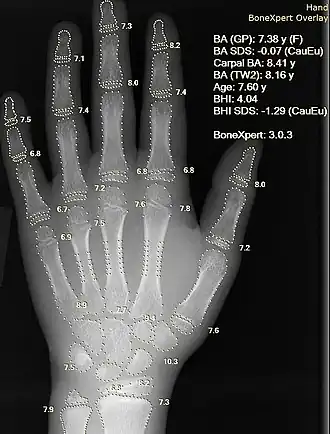

Information can take the form of images, sound, video or other multimedia. Bits of information can be streamed via signals. Its processing is the central notion of informatics, the European view on computing, which studies information processing algorithms independently of the type of information carrier – whether it is electrical, mechanical or biological. This field plays important role in information theory, telecommunications, information engineering and has applications in medical image computing and speech synthesis, among others. What is the lower bound on the complexity of fast Fourier transform algorithms? is one of the unsolved problems in theoretical computer science.

| FFT algorithms | Image processing | Speech recognition | Data compression | Medical image computing | Speech synthesis |